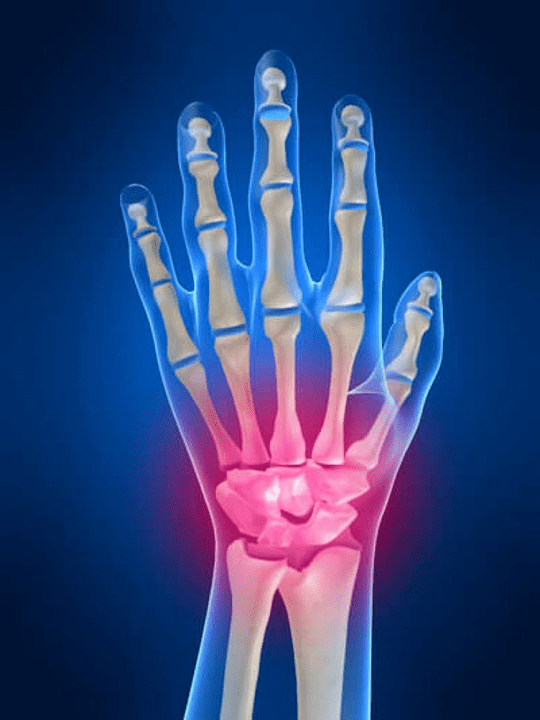

Anatomia das articulações da mão

Todas as articulações da mão são habituais para serem divididas nos seguintes grupos:

- junta do punho;

- articulações do pulso;

- articulações de padrão carpo;

- articulações interpenciais;

- Juntas do Phalanx Parlémal;

- Juntas interfalanx.

A articulação do pulso

A articulação do pulso é formada pelos ossos dos ossos proximais (superior) vários pulsos (Triedral, semi -lua, ossos escafoides) e áreas distais de radiação e ossos do cotovelo. O osso do cotovelo não está diretamente conectado aos ossos do pulso, mas com a ajuda de distal (Mais baixo) o disco articular. Esta estrutura separa a cavidade da articulação do pulso da cavidade distal (Mais baixo) A articulação de ladrilhos.